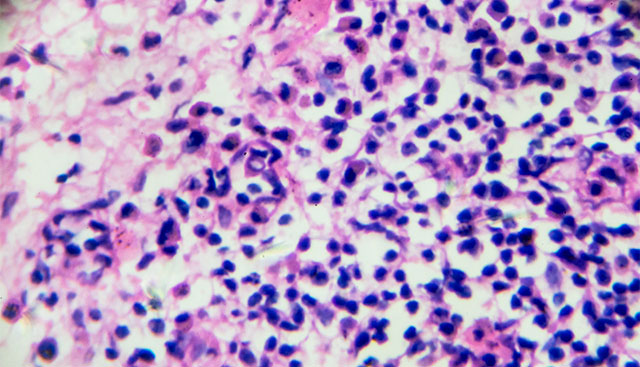

Tumor Infiltrating Lymphocyte Therapy for Solid Tumors

The potential impact TIL therapy can have on cancer patients is monumental, which is why Moffitt Cancer Center has been at the forefront of this...

Tumor Infiltrating Lymphocytes (TILs) Study for Patients with BCG Unresponsive High-Grade Non-Muscle Invasive Bladder Cancer

A clinical trial focuses on adoptive cellular therapy of tumor-infiltrating lymphocytes for BCG Unresponsive High-Grade Non-Muscle Invasive Bladder...